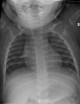

: Neumonía/ Bronquiolitis

: Derrame/ neumonía

: Asma bronquial

: Neumonia lobar

: Timo/ signo de la vela